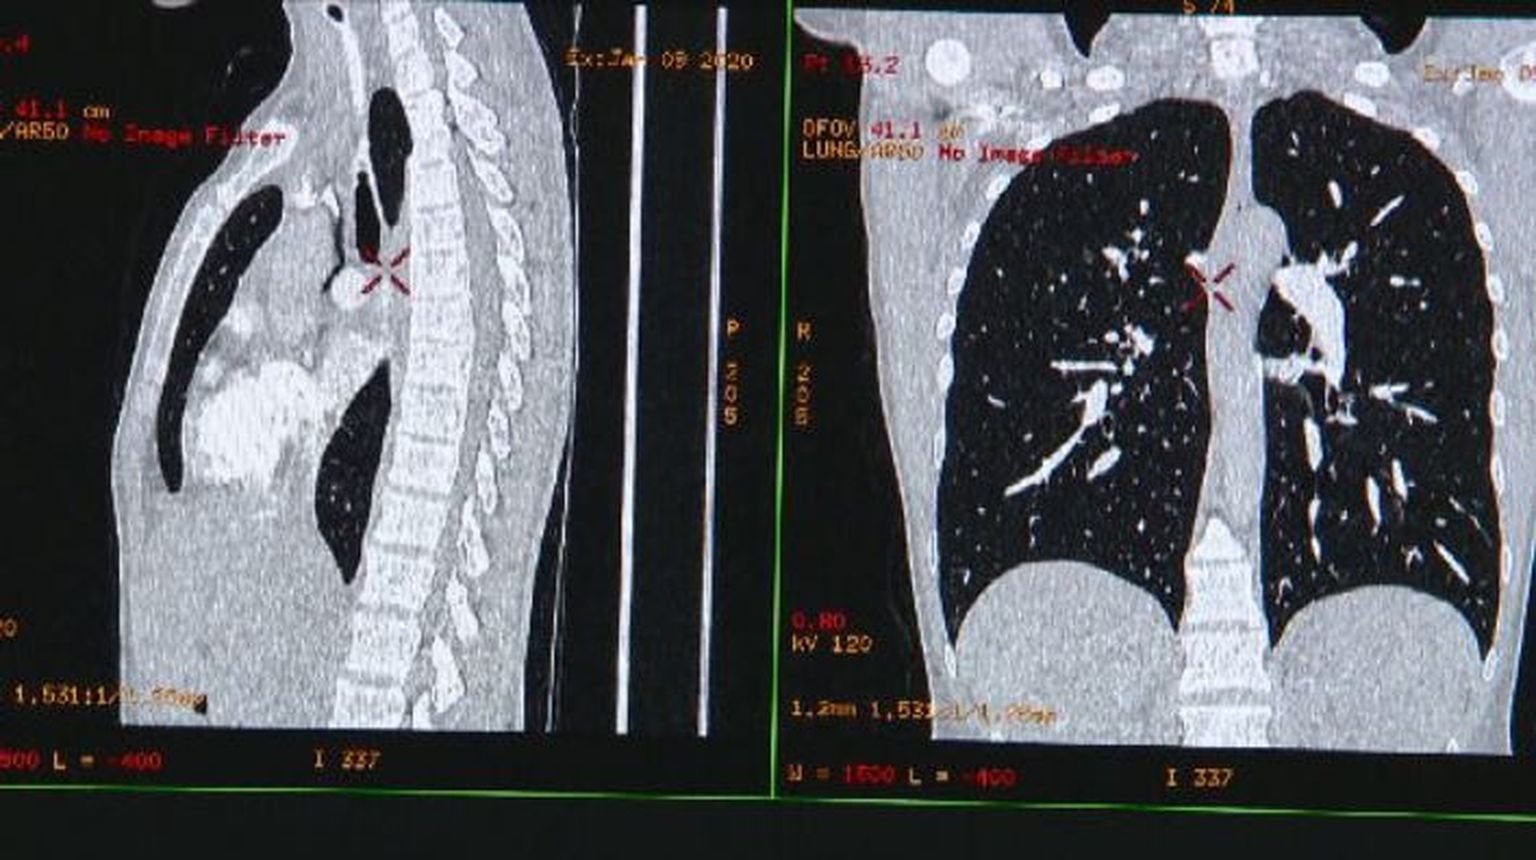

• Snimke raka - 2 Foto: DNEVNIK.hr

• Snimke raka - 1 Foto: DNEVNIK.hr